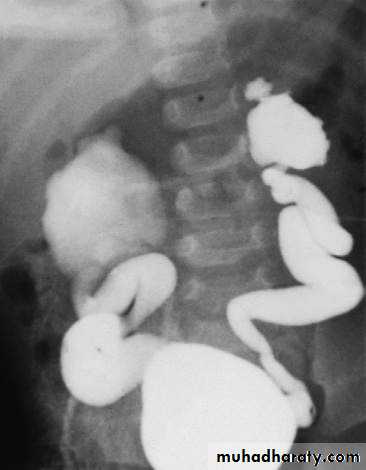

VUR (grade IV) shown by micturating cystogram. The bladder has been filled with contrast medium through a urinary catheter. After micturition there was gross VUR into widely distended ureters and pelvicalyceal systems.